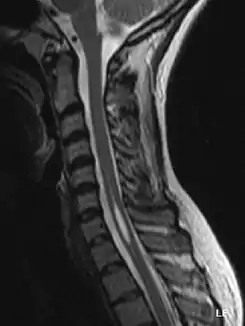

La siringomielia es un trastorno en el cual se forma un quiste dentro de la médula espinal. Este quiste se conoce como siringe o syrinx. Con el tiempo, el syrinx se expande y alarga, destruyendo el centro de la médula espinal. Puesto que la médula espinal conecta el cerebro con los nervios de las extremidades, este daño causa dolores, debilidad y rigidez en la espalda, los hombros, los brazos o las piernas. Otros síntomas pueden incluir dolores de cabeza (cefalea) y pérdida de la capacidad de sentir calor o frío extremos, especialmente en las manos. Cada paciente tiene una combinación distinta de síntomas.

Cerca de 21 mil personas en Estados Unidos sufren de siringomielia. Otras enfermedades comparten los síntomas iniciales de la siringomielia. En el pasado, esto ha dificultado el diagnóstico. Sin embargo, con la resonancia magnética nuclear ha aumentado notablemente el número de casos de siringomielia diagnosticados en las etapas iniciales del trastorno.

Una serie de lesiones pueden obstruir el flujo normal del líquido cefalorraquídeo y redirigirlo hacia la médula espinal. Esto da lugar a la formación del syrinx o siringe, el cual se llena de líquido cefalorraquídeo. Las diferencias de presión a lo largo de la médula espinal hacen que el líquido se mueva dentro del quiste. Se cree que este movimiento continuo del líquido da lugar al crecimiento del quiste y causa daños adicionales a la médula espinal.